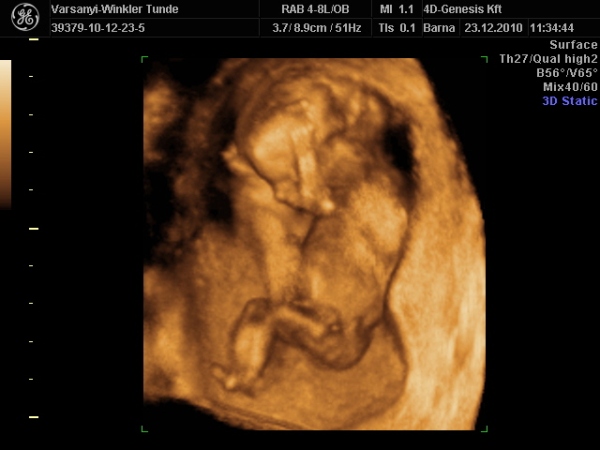

)2010.12.23 11:37